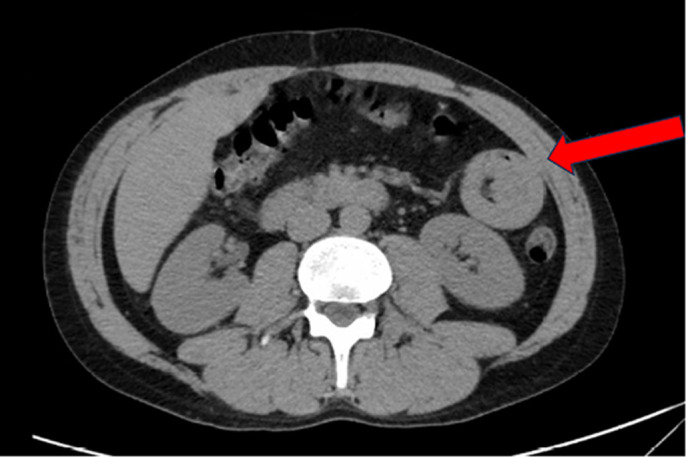

Case presentation: We report a 33-year-old male with a history of surgically treated intussusception and 12 years of marijuana use, who presented to the emergency department (ED) twice with nausea, vomiting, and abdominal pain. After imaging revealed intussusception, the patient underwent multiport-robot-assisted small bowel resection. The patient had no complications and was discharged after 6 days.